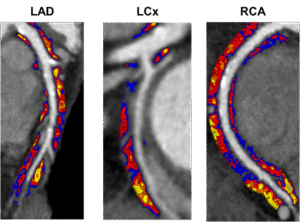

CaRi-Heart uses routine CT coronary angiography (CTCA) to analyse perivascular fat attenuation, a CT-based biomarker of coronary inflammation. This inflammatory signal, quantified as the FAI-ScoreTM, is a powerful measure of active coronary disease biology that cannot be seen on standard CT images. It highlights patients who may appear low risk despite minimal plaque or even a zero calcium score, but who have an elevated risk of future cardiac events. Research studies have shown that an abnormal FAI-Score is associated with a 20-fold increased risk of fatal heart attack and 6 times higher risk for major adverse cardiac events (MACE) (Chan, Lancet 2024).